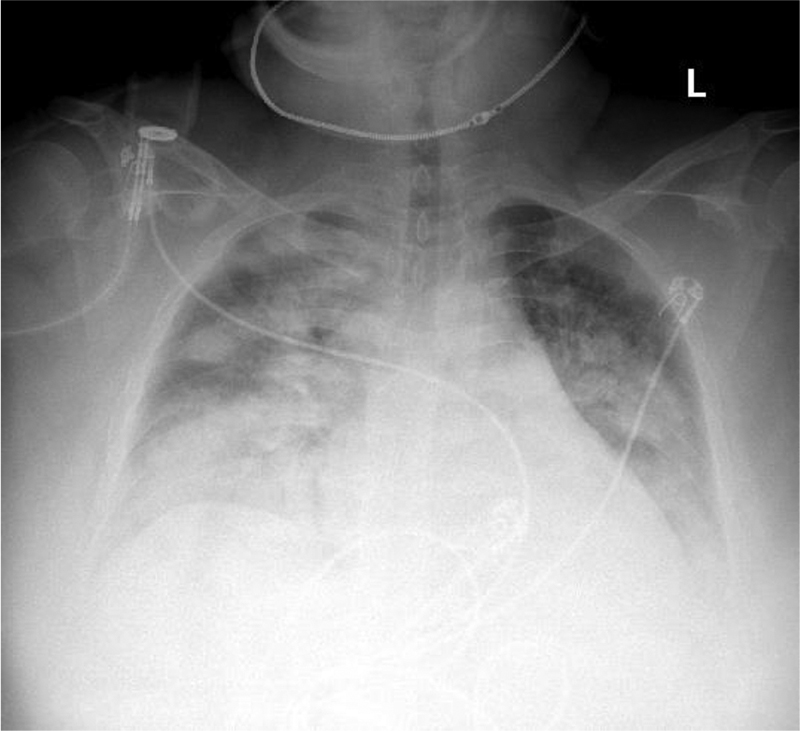

On day 3 of hospitalization, the patient’s fever was 102.3F, and she was started on azithromycin 500 mg IV daily. A repeat chest x-ray revealed retrocardiac opacity, suggesting infectious process (Figure 1). The patient now required 3L by nasal cannula (NC) from room air. Overnight, the patient was found to be tachycardic once again at 118 beats/min, febrile with temperature recorded at 102.9F, and worsening oxygenation increasing from 3L of NC to 15L on a non-rebreather mask saturating 88%. A commuted tomography (CT) of the chest was done to rule out PE; a physical exam noted crackles in bilateral lung fields, and the patient was administered IV Lasix 20 mg. She was also up titrated to high flow nasal cannula at 40L O2 and 60% of FiO2. A chest CT was negative for pulmonary embolism but did reveal bilateral extensive pulmonary consolidations affecting all lobes but most severely involving bilateral lower lobes, consistent with multifocal pneumonia as well as trace bilateral pleural effusions (Figure 2).

Figure 1

Figure 1. Chest X-ray, indicating retro-cardiac opacity and infectious etiology.